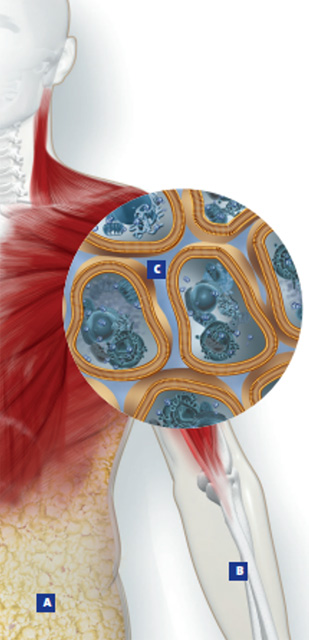

Die Extrazellulärmasse (ECM) umfasst den nicht zellulär gebundenen Anteil der Fettfreien Masse (FFM) und besteht hauptsächlich aus extrazellulärer Flüssigkeit (Plasma und interstitielle Flüssigkeit), den Knochen und aus Bindegewebe. Kurzfristige Veränderungen der ECM sind in der Regel auf Schwankungen der Extrazellulären Flüssigkeiten (ECW) zurückzuführen.

Die Körperzellmasse (BCM) umfasst alle von einer Membran umhüllten stoffwechselaktiven Zellen des Körpers und stellt energetisch betrachtet das «Kraftwerk» des Körpers dar. Die Körperzellmasse umfasst sowohl die Skelettmuskulatur als auch die Zellen der Organe (Nicht-Muskel-BCM). Das Verhältnis von Skelettmuskulatur zu Nicht-Muskel-BCM beträgt beim Gesunden 3.5 :1 bis 4:1.

In der Fettfreien Masse läuft der Grossteil aller physiologisch wichtigen Prozesse ab, während die Fettmasse dem Körper hauptsächlich als Energiespeicher dient. Aus diesem Grund ist eine Analyse der Fettfreien Masse besonders bei kranken Personen von Interesse.

Insbesondere die Hydrationsverteilung in der Fettfreien Masse auf die Intra- bzw. Extrazellulärbereiche (ECW) ermöglicht interessante Schlüsse über den aktuellen Ernährungszustand.

A = Fettmasse

B = Fettfreie Masse inkl. Body Cell Mass

C = Wasserverteilung intra- und extrazellulär